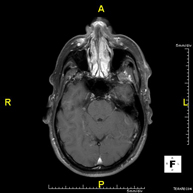

Prueba diagnóstica no invasiva que consiste en la obtención de imágenes de alta definición anatómica del cerebro mediante el empleo de un campo electromagnético y ondas de radio (con un emisor y un receptor). No utiliza radiación ionizante. Indicaciones: problemas vasculares, pérdida de memoria, epilepsia, cefalea, malformaciones, sospecha de tumor, meningitis. - RM Cais

Prueba diagnóstica no invasiva que consiste en la obtención de imágenes de alta definición anatómica del cerebro mediante el empleo de un campo electromagnético y ondas de radio (con un emisor y un receptor). No utiliza radiación ionizante. Se realiza, posteriormente, una medición cualitativa y cuantitativa de varios metabolitos (sustancias), que permitirán caracterizar las lesiones. Indicaciones: tumores, trastornos metabólicos, infecciones, epilepsia.